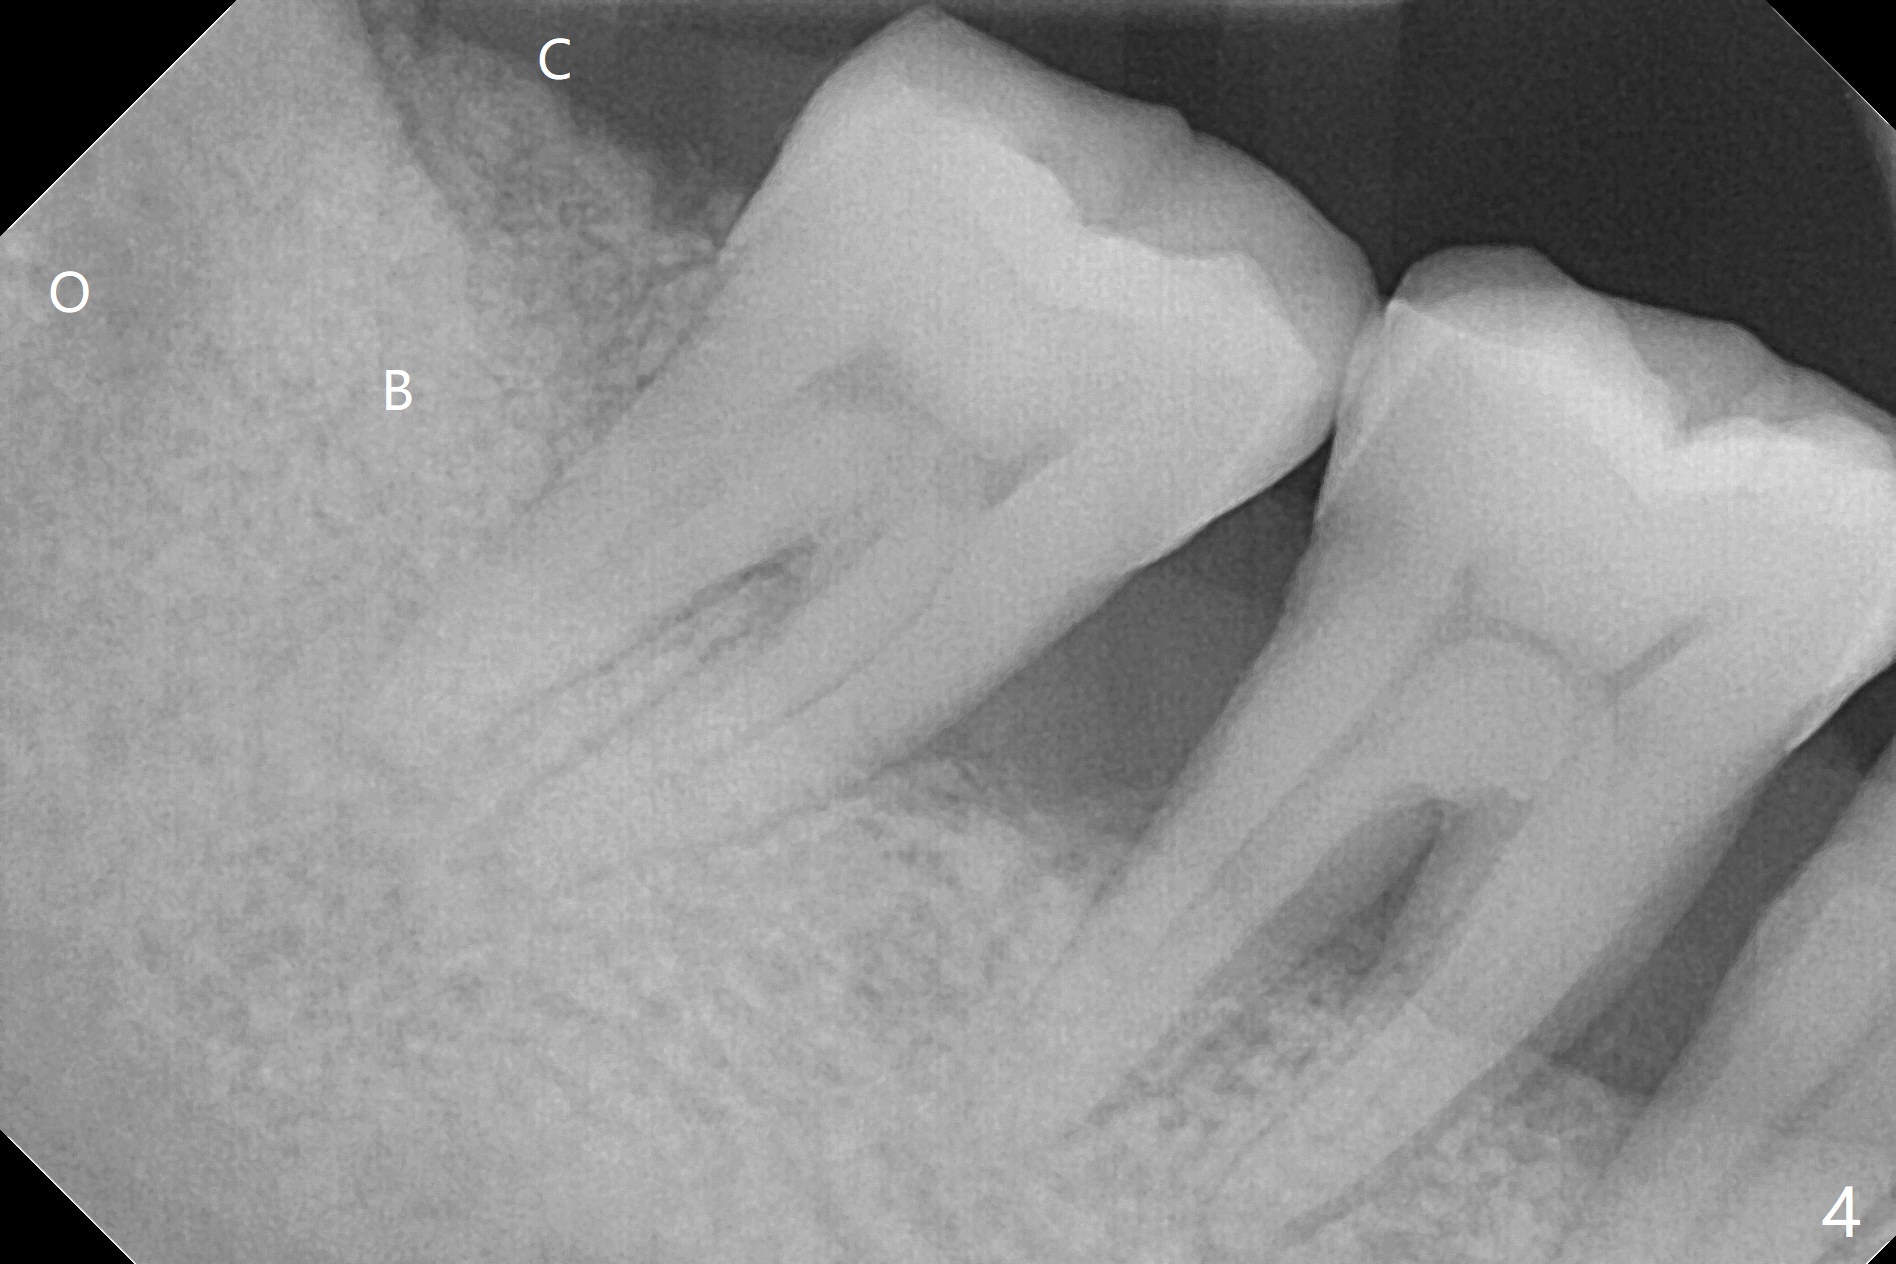

with Severe Bone Loss

A 44-year-old woman (YHM) has generalized moderate localized severe chronic periodontitis (Fig.1). Periodontal abscess develops between the teeth #31 and 32. Since the pain and mobility is more severe at #32 than 31, the former is extracted (Fig.2). After thorough curettage and copious irrigation, Osteogen plug is placed in the distal portion of the socket (Fig.3, 4 O), while allograft in the mesial one (B), with collagen plug on the top (C) before suturing (Fig.5). The tooth #31 is stable and pain-free with formation of new bone distal 7 months postop (Fig.6,6' *), while bone loss at #3 and 4 is more severe.